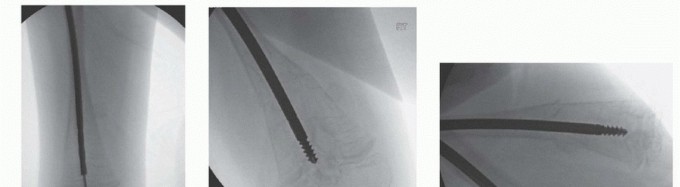

## Guidewire Placement and Osteotomies in the Femur

## Ideally, the tip of the guidewire is placed just medial to the center of the greater trochanter, in line with the shaft of the femur (TECH FIG 1A).

## The wire is then advanced to the first osteotomy site.

## In many cases, it is necessary to angle the wire markedly, both anteriorly and laterally, at first because of the very common severe anterior and lateral bowing of the femur in the subtrochanteric region.

## Osteotomy sites are marked on the skin after visualization with the C-arm, based on preoperative templating and intraoperative visualization (TECH FIG 1B).

## A 1-cm incision is made directly over the anterior lateral apex of the deformity.

## Blunt dissection then is performed with a hemostat down to the periosteum (TECH FIG 1C).

## The periosteum is incised longitudinally with a small osteotome, which is then rotated 90 degrees (TECH FIG 1D).

## An incomplete osteotomy is performed while stability of the leg is maintained manually. The osteotomy is completed with gentle manual pressure, the guidewire is extended to the next osteotomy site, and the process is continued until all deformities are corrected. For severe deformities, an open segmental resection at the apex is necessary to avoid excessive soft tissue tension (see FIGS 2 and 5) on structures such as the sciatic nerve. Rarely are more than two osteotomies required.

## The guidewire is then passed into the distal femur (TECH FIG 1E).

## TECH FIG 1 • A. Guidewire placed through the greater trochanter to the site of the first osteotomy. B. Localization for osteotomy using C-arm. Reaming can be done at the site of the osteotomy to stabilize the proximal segment. C. A 1-cm incision is made over the apex of the osteotomy, and the soft tissues are spread to the periosteum. D. The osteotome is rotated and the osteotomy completed. Gentle manual traction and use of a lever such as a padded mallet will help to gently align and complete the osteotomy site. E. Guidewire in the distal femur.